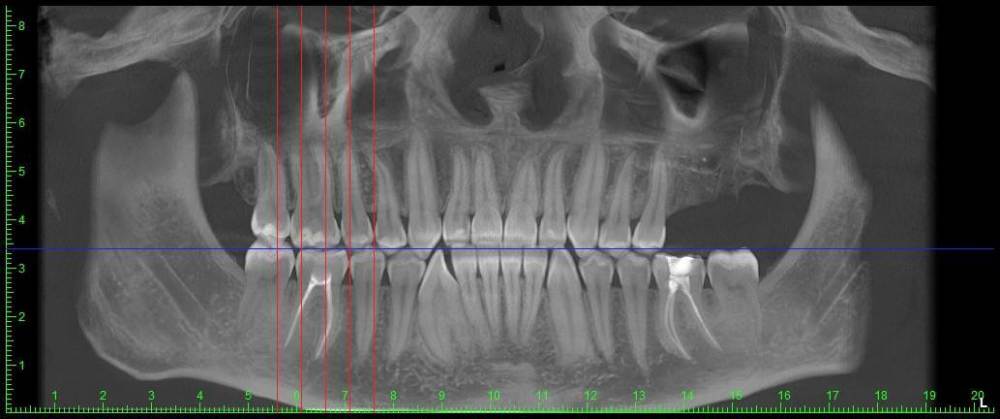

podivilov Опубликовано 14 января, 2024 Поделиться Опубликовано 14 января, 2024 (изменено) На этой неделе лечил два зуба — нижнюю шестёрку с левой стороны и нижнюю шестёрку с правой стороны. Левая шестёрка успешно вылечена, ничего не болит. С правой же проблемы. Лечение правой шестёрки начали в эту среду, закончили лечение в пятницу. Всего было два приёма. После первого приёма, когда поставили временную пломбу с лекарством, зуб начал ныть — да так, что ночью несколько раз просыпался. Тогда нерв ещё не был удалён, поэтому я просто сообщил об этом лечащему стоматологу, — сказали, что всё нормально. В пятницу после завершения лечения думал, что всё, больше болеть не будет — болеть ведь нечему, нерв удалён и каналы запломбированы. Лечили за два приёма, последний приём длился два с половиной часа. После того, как отошла заморозка, действительно ничего не болело. Порадоваться этому успел ровно до ночи: к этому моменту ноющая боль вернулась. Думал, что так и должно быть, и просто лёг спать. В итоге и вчера, и сегодня ноющая боль сохраняется. Причём достаточно интенсивная — не слабая. Сильнее, чем была до лечения зуба. Острой боли нет, даже если нажимать на зуб. Боль усиливается ближе к ночи. Иногда кажется, будто ноет также верхний зуб на той же стороне челюсти. На сладкое и холодное зубы не реагируют, просто в течение дня сохраняется сильная ноющая боль. Почему-то не помогают даже обезболивающие — пробовал «Нурофен» и «Кетанов», но какого-то особого эффекта не ощутил. Был сегодня на приёме у другого стоматолога, где мне сделали КЛКТ снимок. На снимке ничего страшного не обнаружили — сказали, что корни запломбированы хорошо. Стоматолог сказал, что может распломбировать зуб и запломбировать заново, но предупредил, что боли могут пройти сами, и, вероятно, нет смысла сейчас что-либо делать. Загрузил на Google Drive КЛКТ снимок, сделанный сегодня (с просмотровщиком Planmeca Romexis): https://drive.google.com/file/d/1t5zrJj8r3p1SG44UCOw2RGo5PJQxerh4/view?usp=sharing Изменено 14 января, 2024 пользователем podivilov Дополнение Ссылка на комментарий

wladdX Опубликовано 14 января, 2024 Поделиться Опубликовано 14 января, 2024 Корневые каналы заполнены адекватно, на мой взгляд Ссылка на комментарий